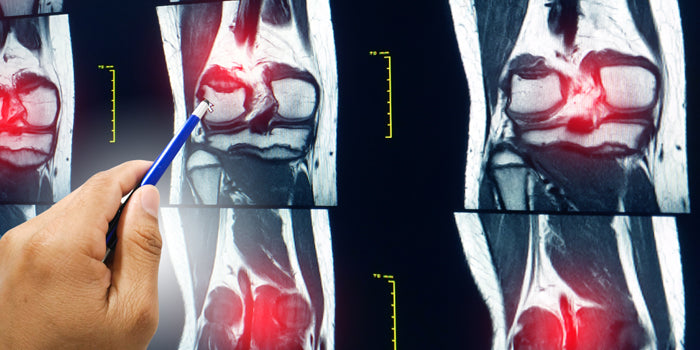

Once accessed by the on-staff physician, I was told it was probably a tear somewhere in the knee, but we couldn't be sure of that or the extent of it until the swelling went down. I'd be able to go for an MRI in the following two to three weeks. SWEET. They wrapped me up, and after a quick lesson in the hospital hallway on how to use crutches, I was sent on my way. "Have they started benching yet?" was the first question I remember asking as I left the hospital, almost tripping over my crutch. I had it already in my head that I wanted to keep going, at least take a token bench and deadlift to secure a total in the meet I had moved countries to train for—I moved from Toronto, Ontario to Cincinnati, Ohio. You only live once anyway, and who knew, maybe my knee wasn't so bad. Once I arrived back in the warm-up room with plenty of time to spare until the start of bench, I only had one thing on my mind: get in my shirt and keep going! I would take my original opener as a second after a token first attempt to secure a run at deadlifts. I received quite a few stares as I was limping around trying to warm up in my shirt and crutches. I felt as though people assumed I was dumb for coming back to keep lifting. They weren't completely wrong: I knew what I was doing was risky, but I wasn't going to be completely taken out by just a little bum knee. And in the words of Roger Alan Wade, "If you're gonna be dumb, you gotta be tough." This is who I am! Despite my right leg not being able to fully cock back into my normal bench setup, my first attempt went great. I put my shirt on for my second, and again, the right knee being out of position, I was able to get my original planned bench opener. After being on the fence about taking a third and possibly getting a two-pound PR over my best bench in competition, I decided to go for it. I was here to do my best, and in my head at the time, the worst that could happen was dumping the bar for the spotters to catch. At that rate, a deadlift PR would not have been a thing, as my knee had started to hurt more and more. Do you know what the sound of a broom makes when it cracks in half? That's kind of what I and I think a lot of people heard when I realized my arm was no longer doing normal arm stuff. ARE YOU FUCKING KIDDING ME? In so much shock, I walked off the platform, gripping my left wrist and forearm without a limp in my step anymore. Fast forward through the fit of anger in the back hallway on the way to the hospital (this time in an ambulance!). I asked not to be taken to the same one as last time because I was embarrassed the lady at the front desk would recognize me. Thankfully the doctors took care of me quickly and pushed for immediate surgery the following morning. I left with a thick plate in both my ulna and radius, held in with seven screws each, and two impressive scars on both sides of my forearm. [gallery columns="2" ids="https://www.elitefts.com/wp/wp-content/uploads/2021/01/ChanelArm1.png|,https://www.elitefts.com/wp/wp-content/uploads/2021/01/ChanelArm2.png|,https://www.elitefts.com/wp/wp-content/uploads/2021/01/ChanelArm3.png|,https://www.elitefts.com/wp/wp-content/uploads/2021/01/ChanelArm4.png|"] As you can see, the bench shirt stayed on. We were able to pull it off without damaging it, and I still use it to this day. All this may seem a little sensationalized, but this is really the gist of how the day unfolded and how it felt. I've left many personal details out and highlighted what I think was needed to be shared to explain my headspace. Now, to get into how someone can come back from a day like that. Tons of people have broken bones and torn muscles and ligaments before, in and out of competition, and this is just one of those stories. The healing process for injuries can differ from person to person. Depending on age, fitness level, overall health, and sex. It’s assumed that a young, healthy, athletic male could have an easier time healing from major injuries than a little old grandma. So for reference, at the time of the injuries, I was 27 years old, nesting comfortably in the "maybe she'll come back, maybe she won't" group. The first two to three weeks were rough. I couldn't walk down a set of stairs (butt walking was a thing) or walk with my crutches for more than a few minutes without major arm pain. Sleeping was a no, getting in and out of bed caused immense pain, getting in and out of cars was a ten-step process, the list goes on... Day to day tasks we take for granted had now become a huge chore. I couldn't even shower, wash my hair, or sit on the toilet without having to worry about how I was going to do it and who I could ask for help. How's a girl supposed to poop around here? One of the best things I did for myself was to start loading up on calcium and vitamin D right away. I found good results from a good diet filled with protein as well. Water was essential as always, about a gallon a day or more. My diet was pretty much what you would expect it to be while trying to make muscle gains during an offseason or heavy training cycle. I gained a little extra weight, but ultimately I really wanted to make sure my body had everything needed to heal. Around the three-week post-op mark, I had started going to the gym and doing anything moderate I could to get blood flow into my leg. At the time, I was still giving my arm a little more time. If it hurt, I shut it down or tried something else. I never pushed through the pain. I did a lot of simple knee stabilizing exercises; heel elevated step-ups to a very low step, high box squats with minimal weight (if any), Zercher harness conventional deadlifts from pins above the knee, stiff leg deadlifts with light weights, etc. I did these for another month or so, increasing the weight if it didn't hurt. I will mention to anyone going through a similar situation; you're going to need to be patient with yourself. The number of times I wanted to stop, cry, and crawl home were weekly, if not daily events. I didn't get an MRI until about five weeks in, where the doctor told me it was a full ACL tear and some medial meniscus damage. I opted not to go for surgery because, at that point, I was already feeling stable again from the exercises I was doing and didn't want to be out for another six to eight months. The first time I benched the bar again was around four weeks post-op. I would be lying if I said it was easy to get under the bar again. I knew if I wanted to get back to the sport I loved the most, I needed to remove all doubt in myself. A wise training partner once said to me, "Powerlifting is 90% mental, and the rest is just in your head," and this was no exception to that statement. From there, once or twice a week, I was able to take a bit more weight than the week prior. I started to throw two to four accessories into my sessions, mostly consisting of isolating and controlled vertical movements: things like single-arm dumbbell floor presses, single-arm pulldowns and rows, light tricep pushdowns on the assisted dip machine, and high straight bar cable rows. The weight started to build back up with time, but I would shut any movement down that hurt deep into my bones. Around the two-month mark, I decided it was time to focus on a new goal. I chose to sign up for a raw meet about six months post-op, feeling confident if I focused on having fun and not pushing past my comfort zone this time, it would ultimately also help my mental game. The idea at the time was the sooner I got back up on the horse, the better... During this time, I was still eating extra protein and taking calcium every day and had massage therapy done on my arm at least once a month. I also had at least two more X-rays done of my arm to ensure progress and new bone growth was taking place. I started including other exercises in waves and stuck to more of a 5x5 style program. When it came time to peak for the meet, I planned to phase out the volume and work up to moderate singles on main movements. At the time, deadlifting conventional was my best option because the pressure on my knee to perform sumo was too risky. I also switched from right hand over/left arm under to right arm under/left arm over because my arm didn't want to supinate like that yet. If you're returning from a major injury and want to find a meet to do, do one close to your heart. The amount of love I have for Laura Phelps and what she has done for me as a lifter meant one thing: the meet I do every year, surrounded by and competing with all my friends and sisters, would be my comeback meet (Laura’s annual Women’s Pro-Am). The emotional build-up was real. I cried getting my rack height, and I was terrified of people watching me. “What if I broke something again? What if my knee blows out on squats?” These thoughts sometimes still haunt me to this day but are almost completely gone now. I’m proud of how I performed at my first meet back, nine for nine, only six months post-op. Getting back into my gear after a big break was a mindfuck, but it wasn’t impossible. I took my time and sprinkled just a little bit of crazy on top. I’m not suggesting throwing on a suit and havin' at her with some reverse bands right out of the gate, but I would suggest listening to your body and not always to the fear in your head. The mind has evolved to keep you safe for longer than any society has existed. Sometimes it’s up to us to determine when the fear is valid and when it is in the way of the bigger picture. What seemed to be a good progression for me was a slow build-up in my gear. Here is the general outline of how I introduced my gear back into a conjugate style program: